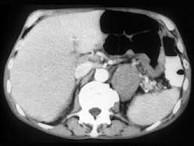

问题 男,57岁,腹部隐痛不适伴低热2月余,腋下可触及数个肿大的淋巴结,请结合图像,作出诊断()

选项 A.左侧肾上腺癌并胃脾转移 B.左侧恶性嗜铬细胞瘤侵及胃脾 C.左侧肾上腺淋巴瘤且胃脾受累 D.左侧肾上腺腺瘤 E.左侧肾上腺转移瘤

答案 C